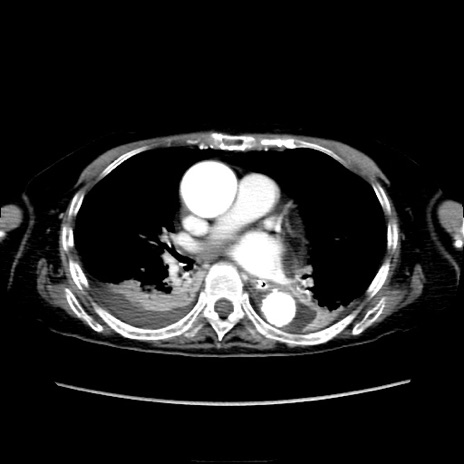

症例40(横断像)

【症例】90歳代女性

【主訴】腹痛・嘔吐

【現病歴】 食欲低下、嘔吐があり昨日他院受診。肺炎と診断され入院となる。入院後より腹部全体に圧痛あり。胃管留置され経過みていたが、症状持続するため、

当院転院となる。

【既往歴】胸椎圧迫骨折、胆石症

【身体所見】腹部:中央に激痛あり、圧痛あり、反跳痛不明

【データ】WBC 17100、CRP 18.82

横断像